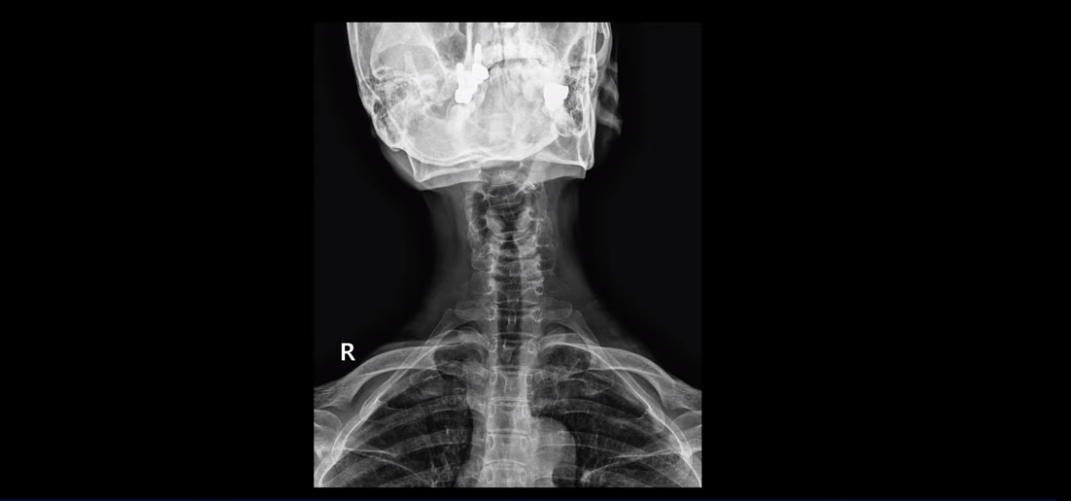

이분 목 X-ray를 보면 역C자형의 목에 전방전위도 보이고,

목도 많이 휘어 보입니다.